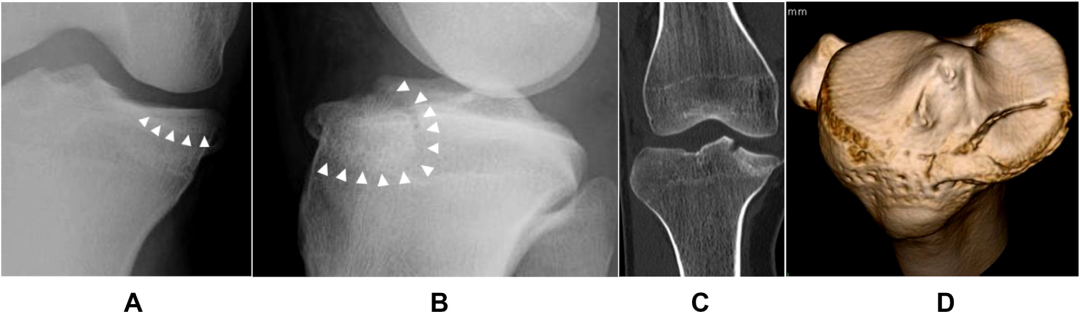

胫骨平台关节面不仅承担下肢负重和应力传导,还参与维持膝关节的正常活动度,关节面复位质量对膝关节功能的恢复十分重要。大多数学者倾向于复位后关节面台阶或分离不应超过2~4 mm。

胫骨平台宽度是膝关节正位片上胫骨近端关节面内缘至其外缘的距离。伴 有外侧平台关节面塌陷的胫骨平台骨折常伴有平台增宽,随着关节面复位,平台宽度大多恢复正常。 因此,平台宽度也成为评估关节面复位质量的间接指标,并与患者长期预后相关。

胫骨平台后倾角是矢状面上胫骨平台关节面与胫骨干垂线的夹角。根据胫骨平台骨折三维损伤机制分型,屈曲型损伤的胫骨平台后倾角增加,而过伸型损伤的胫骨平台后倾角减小或消失,甚至为负值。后倾角的变化既可能仅局限于内侧或外侧平台,也可能同时累及双侧平台,在骨折复位时要针对性恢复对应平台的后倾角。